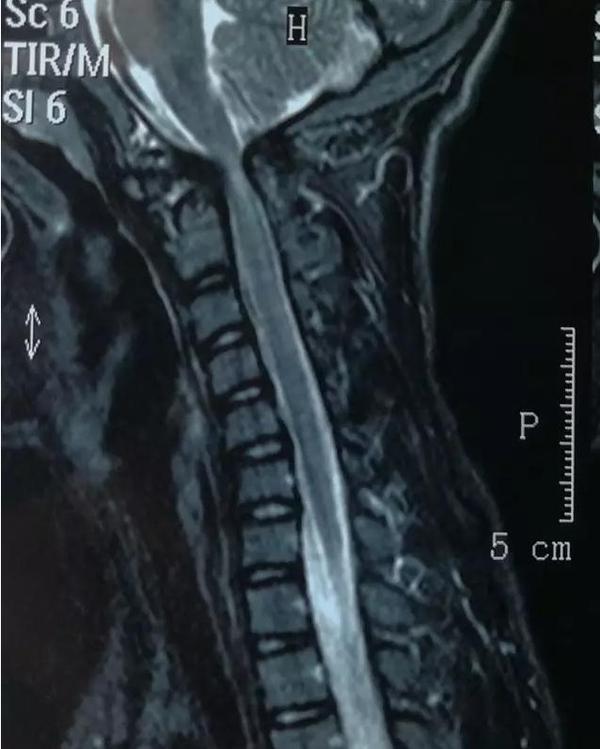

术前影像资料

1、脊髓损伤

2、颅颈畸形:寰枢椎半脱位,齿状突不连续

3、分析术前影像,本例为先天性颅颈畸形,外伤是导致其病情加重的诱因。理由:齿状突小骨和颈2椎体有皮质骨面;颈2变异,为先天性畸形证。